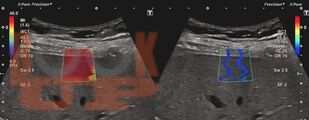

Учебное пособие содержит материал, характеризующий технологию ультразвуковой эластографии. Подробно описана методика проведения эластографии для печени и поверхностно расположенных органов. Представлены данные использования ультразвуковой эластографии в диагностических алгоритмах диффузных заболеваний печени, образований щитовидной и молочной желез с учетом клинических рекомендаций. Отдельное внимание уделено факторам, влияющим на результаты исследования. Представлен протокол эластографии сдвиговой волны печени. Приведены клинические примеры.